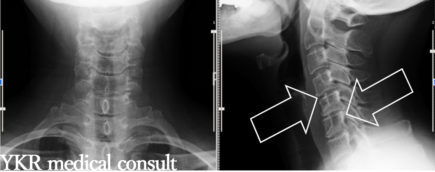

中心性頸髄損傷と交通事故との因果関係(非該当→11級認定)1 依頼内容content事故内容本件事故では、信号待ちのために停車していた被害車両に加害者が被害車両を確認しないまま加害車両を発進させ、被害者が後部座席に乗車し […]

交通事故による頸椎捻挫についての自賠責保険後遺障害の認定(非該当→14級9号認定)1 依頼内容content・事故内容信号機のない住宅街のT字路交差点において、被害者が歩行中、前方から加害車両が右折をしようとして、歩行中 […]